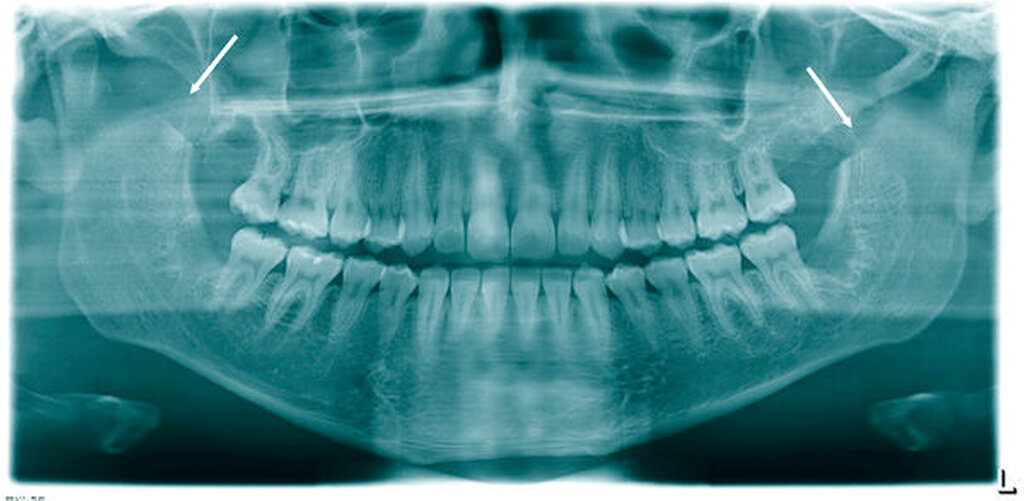

Der Patient erhielt daraufhin als konventionelle Röntgendiagnostik ein Orthopantomogramm (OPG). Hier bestätigte sich die Verdachtsdiagnose einer ausgeprägten, beidseitigen Elongation des Proc. coronoideus (Abbildung 2). Nebenbefundlich zeigten sich die vier Weisheitszähne retiniert.

Präoperativ führten wir zur exakten Eingriffsplanung eine Computertomografie durch. Hier zeigte sich erneut die ausgeprägte Verlängerung der Fortsätze (Abbildung 5). Intraoperativ konnte beim Patienten nach beidseitiger Resektion bereits eine SKD von 44 mm erreicht werden (Abbildung 6). Die Weisheitszahnentfernung erfolgte nun problemlos. Das postoperativ angefertigte OPG zeigt die Resektionsflächen beidseits (Abbildung 7).

Bei der Planung der Operation ist eine suffiziente Bildgebung unerlässlich. Das OPG sowie das dynamische OPG können bereits wichtige Informationen zu Länge und Form des Processus geben. Allerdings empfehlen wir zur genauen Darstellung von Länge, Breite, Struktur und Lage der anatomischen Nachbarstrukturen eine dreidimensionale Darstellung mittels CT oder DVT [Robiony et al., 2012]. Die dreidimensionale radiologische Diagnostik wird in der Regel vom MKG-Chirurgen bei entsprechendem Symptomkomplex (1. Mundöffnungseinschränkung, 2. keine Hinweise für eine Kiefergelenkspathologie, 3. Schmerzsensationen im Bereich des Jochbeins bei forcierter Mundöffnung, 4. keine Besserungstendenz nach initiierter konservativer Therapie) in die Wege geleitet [Kim et al., 2012].